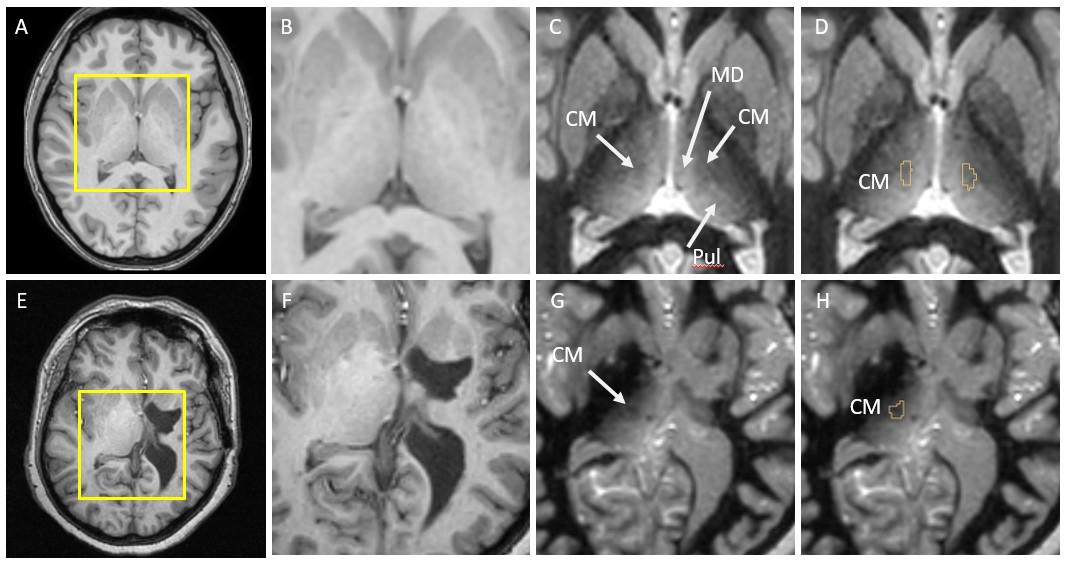

Figure 1 shows the comparison of standard T1 data (B,F) vs. WMn FGATIR data (C,G) on two patients. The second patient (lower panel) shows clear structural brain abnormalities. Note the clear visualization of the CM nucleus as a hypointense triangular notch between the MD and Pul nuclei in WMn compared to T1. THOMAS segmentation of the CM nucleus overlaid on WMn is shown in the rightmost panels (D,H). THOMAS is able to segment the CM nucleus accurately even in cases of significant morphological distortions (lower panel).

Figure 1. Comparison of standard T1 data (B,F) vs. WMn FGATIR data (C,G) on two patients with the THOMAS patient-specific segmentation overlaid on WMn data shown in (D,H). Note the clear visualization of CM in WMn data and accurate segmentation even in the presence of abnormal anatomy (lower panel)